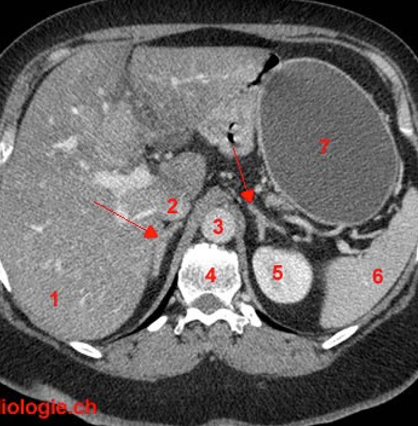

Reconnaître les surrénales à la tomodensitométrie abdominale

Forme de Y ou V inversé (accent circonflexe)

* Identifiées par les flèches rouges sur la photo *